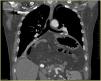

Se realizó radiografía de tórax (fig. 1) objetivándose la presencia de una cámara aérea ocupando ambos hemitórax, sugestivo de herniación gástrica o colónica. La tomografía computarizada (fig. 2) confirmó una hernia hiatal compleja tipo IV, que contiene la totalidad del estómago, duodeno, yeyuno, páncreas parcialmente y colon. El estómago se halló dilatado y rotado, sugestivo de vólvulo gástrico, aunque con adecuada captación parietal.